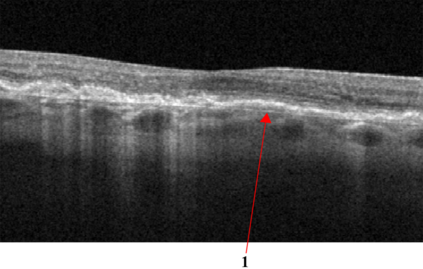

Optical coherence tomography (OCT) is a non-invasive imaging technique with extensive clinical applications in ophthalmology. OCT enables the visualization of the retinal layers, playing a vital role in the early detection and monitoring of retinal diseases. OCT uses the principle of light wave interference to create detailed images of the retinal microstructures, making it a valuable tool for diagnosing ocular conditions. This work presents an open-access OCT dataset (OCTDL) comprising over 1600 high-resolution OCT images labeled according to disease group and retinal pathology. The dataset consists of OCT records of patients with Age-related Macular Degeneration (AMD), Diabetic Macular Edema (DME), Epiretinal Membrane (ERM), Retinal Artery Occlusion (RAO), Retinal Vein Occlusion (RVO), and Vitreomacular Interface Disease (VID). The images were acquired with an Optovue Avanti RTVue XR using raster scanning protocols with dynamic scan length and image resolution. Each retinal b-scan was acquired by centering on the fovea and interpreted and cataloged by an experienced retinal specialist. In this work, we applied Deep Learning classification techniques to this new open-access dataset.